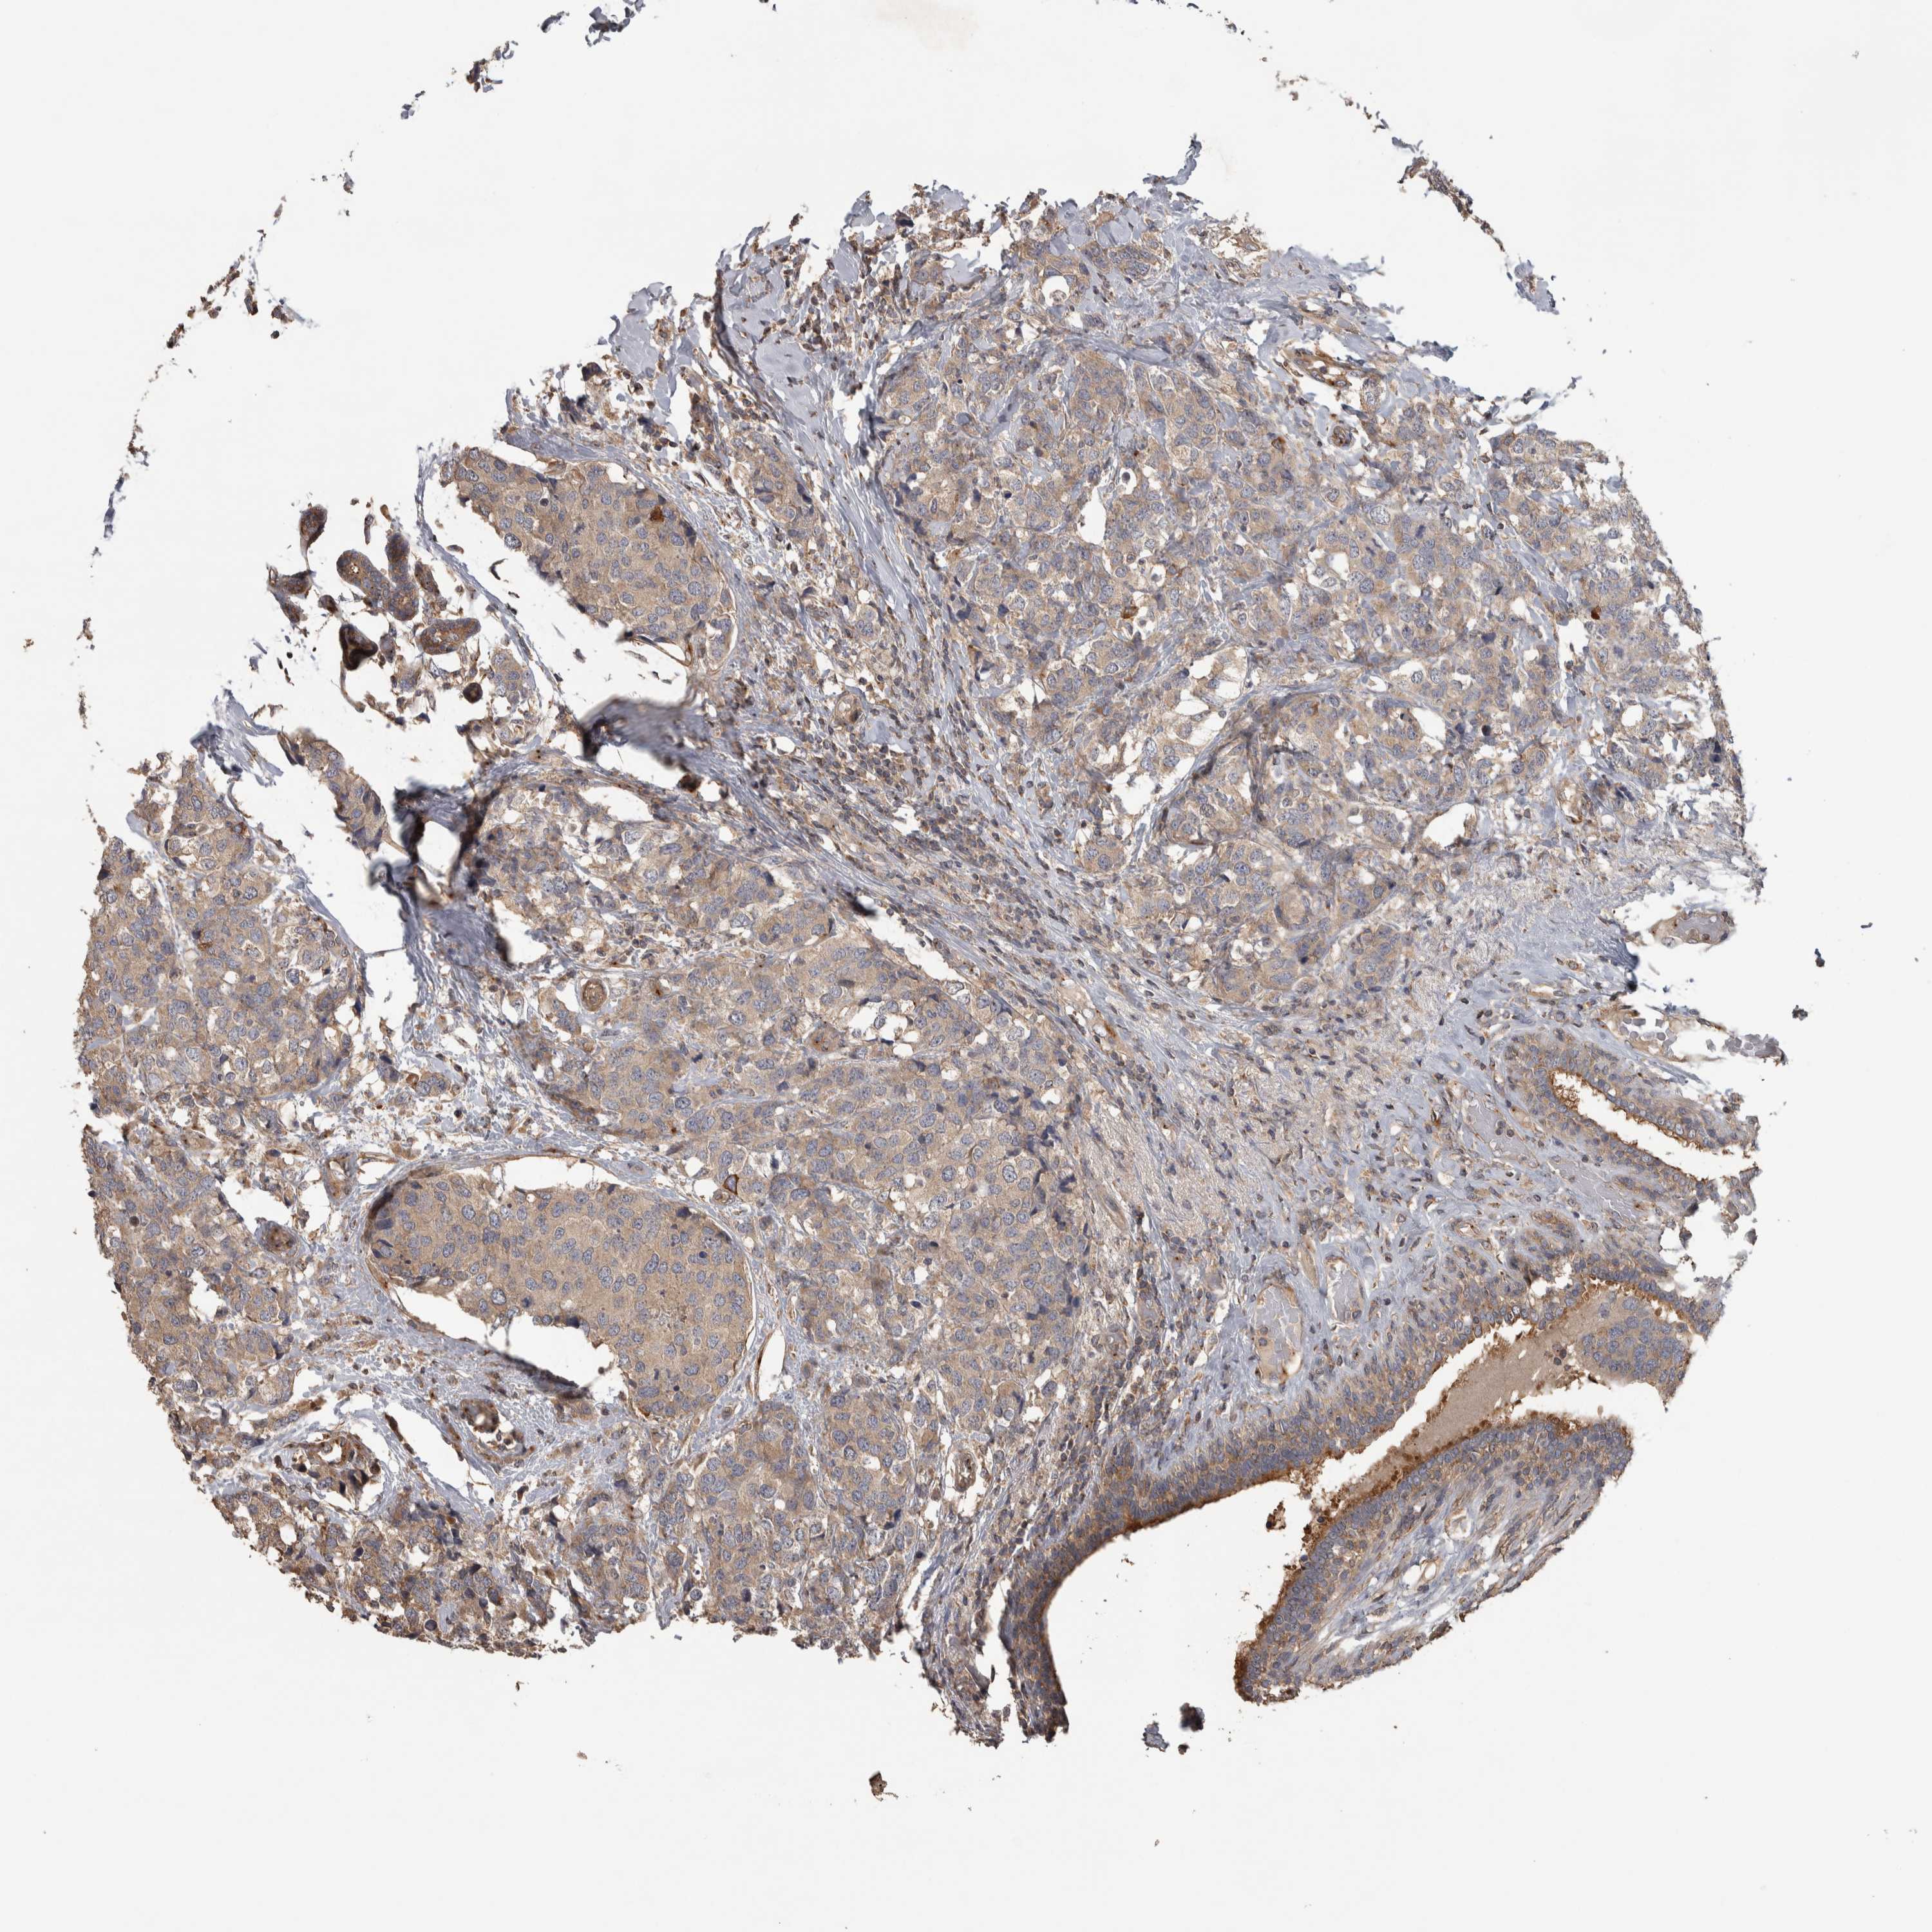

CANCER BREAST CANCER Show tissue menu

BRCA TCGA BRCA VALIDATION PROTEIN EXPRESSION